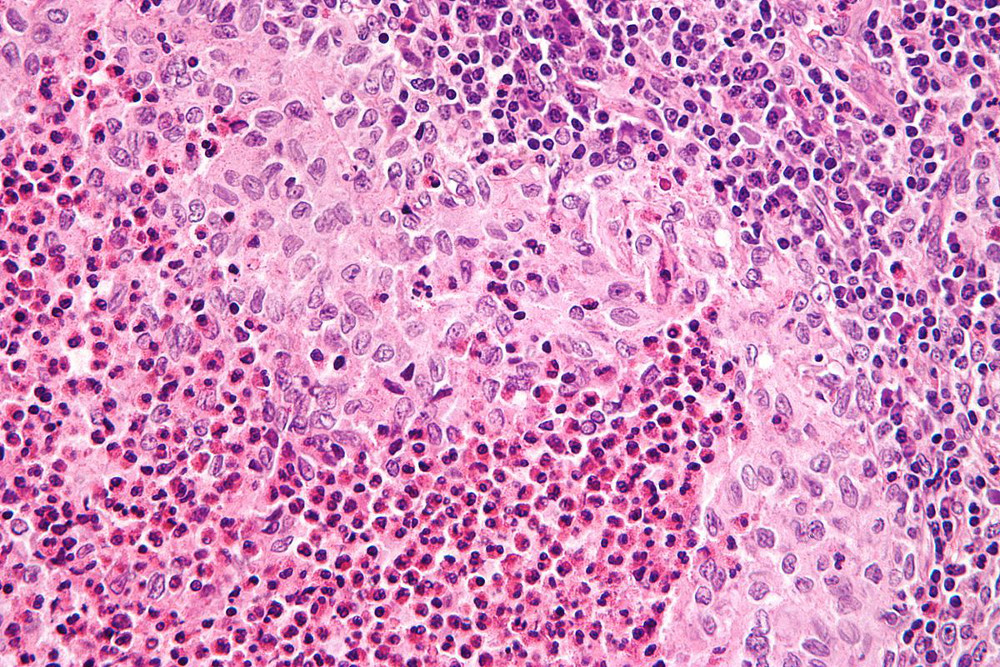

A HCL é caracterizada por lesões granulomatosas que contêm proliferação clonal de células de Langerhans patológicas, que expressam CD1a, CD207 (langerina) e S100. As células HCL são grandes, com um núcleo em forma de rim.[14][Figure caption and citation for the preceding image starts]: Micrografia de ampliação muito alta de histiocitose das células de Langerhans. Coloração H&E. Caracteriza-se por histiócitos do tipo Langerhans que possuem núcleo reniforme (em forma de rim) e coram com S100 e CD1aNephron. Reproduzido sob uma licença Creative Commons CC BY-SA 3.0: https://creativecommons.org/licenses/by-sa/3.0/deed.en [Citation ends].